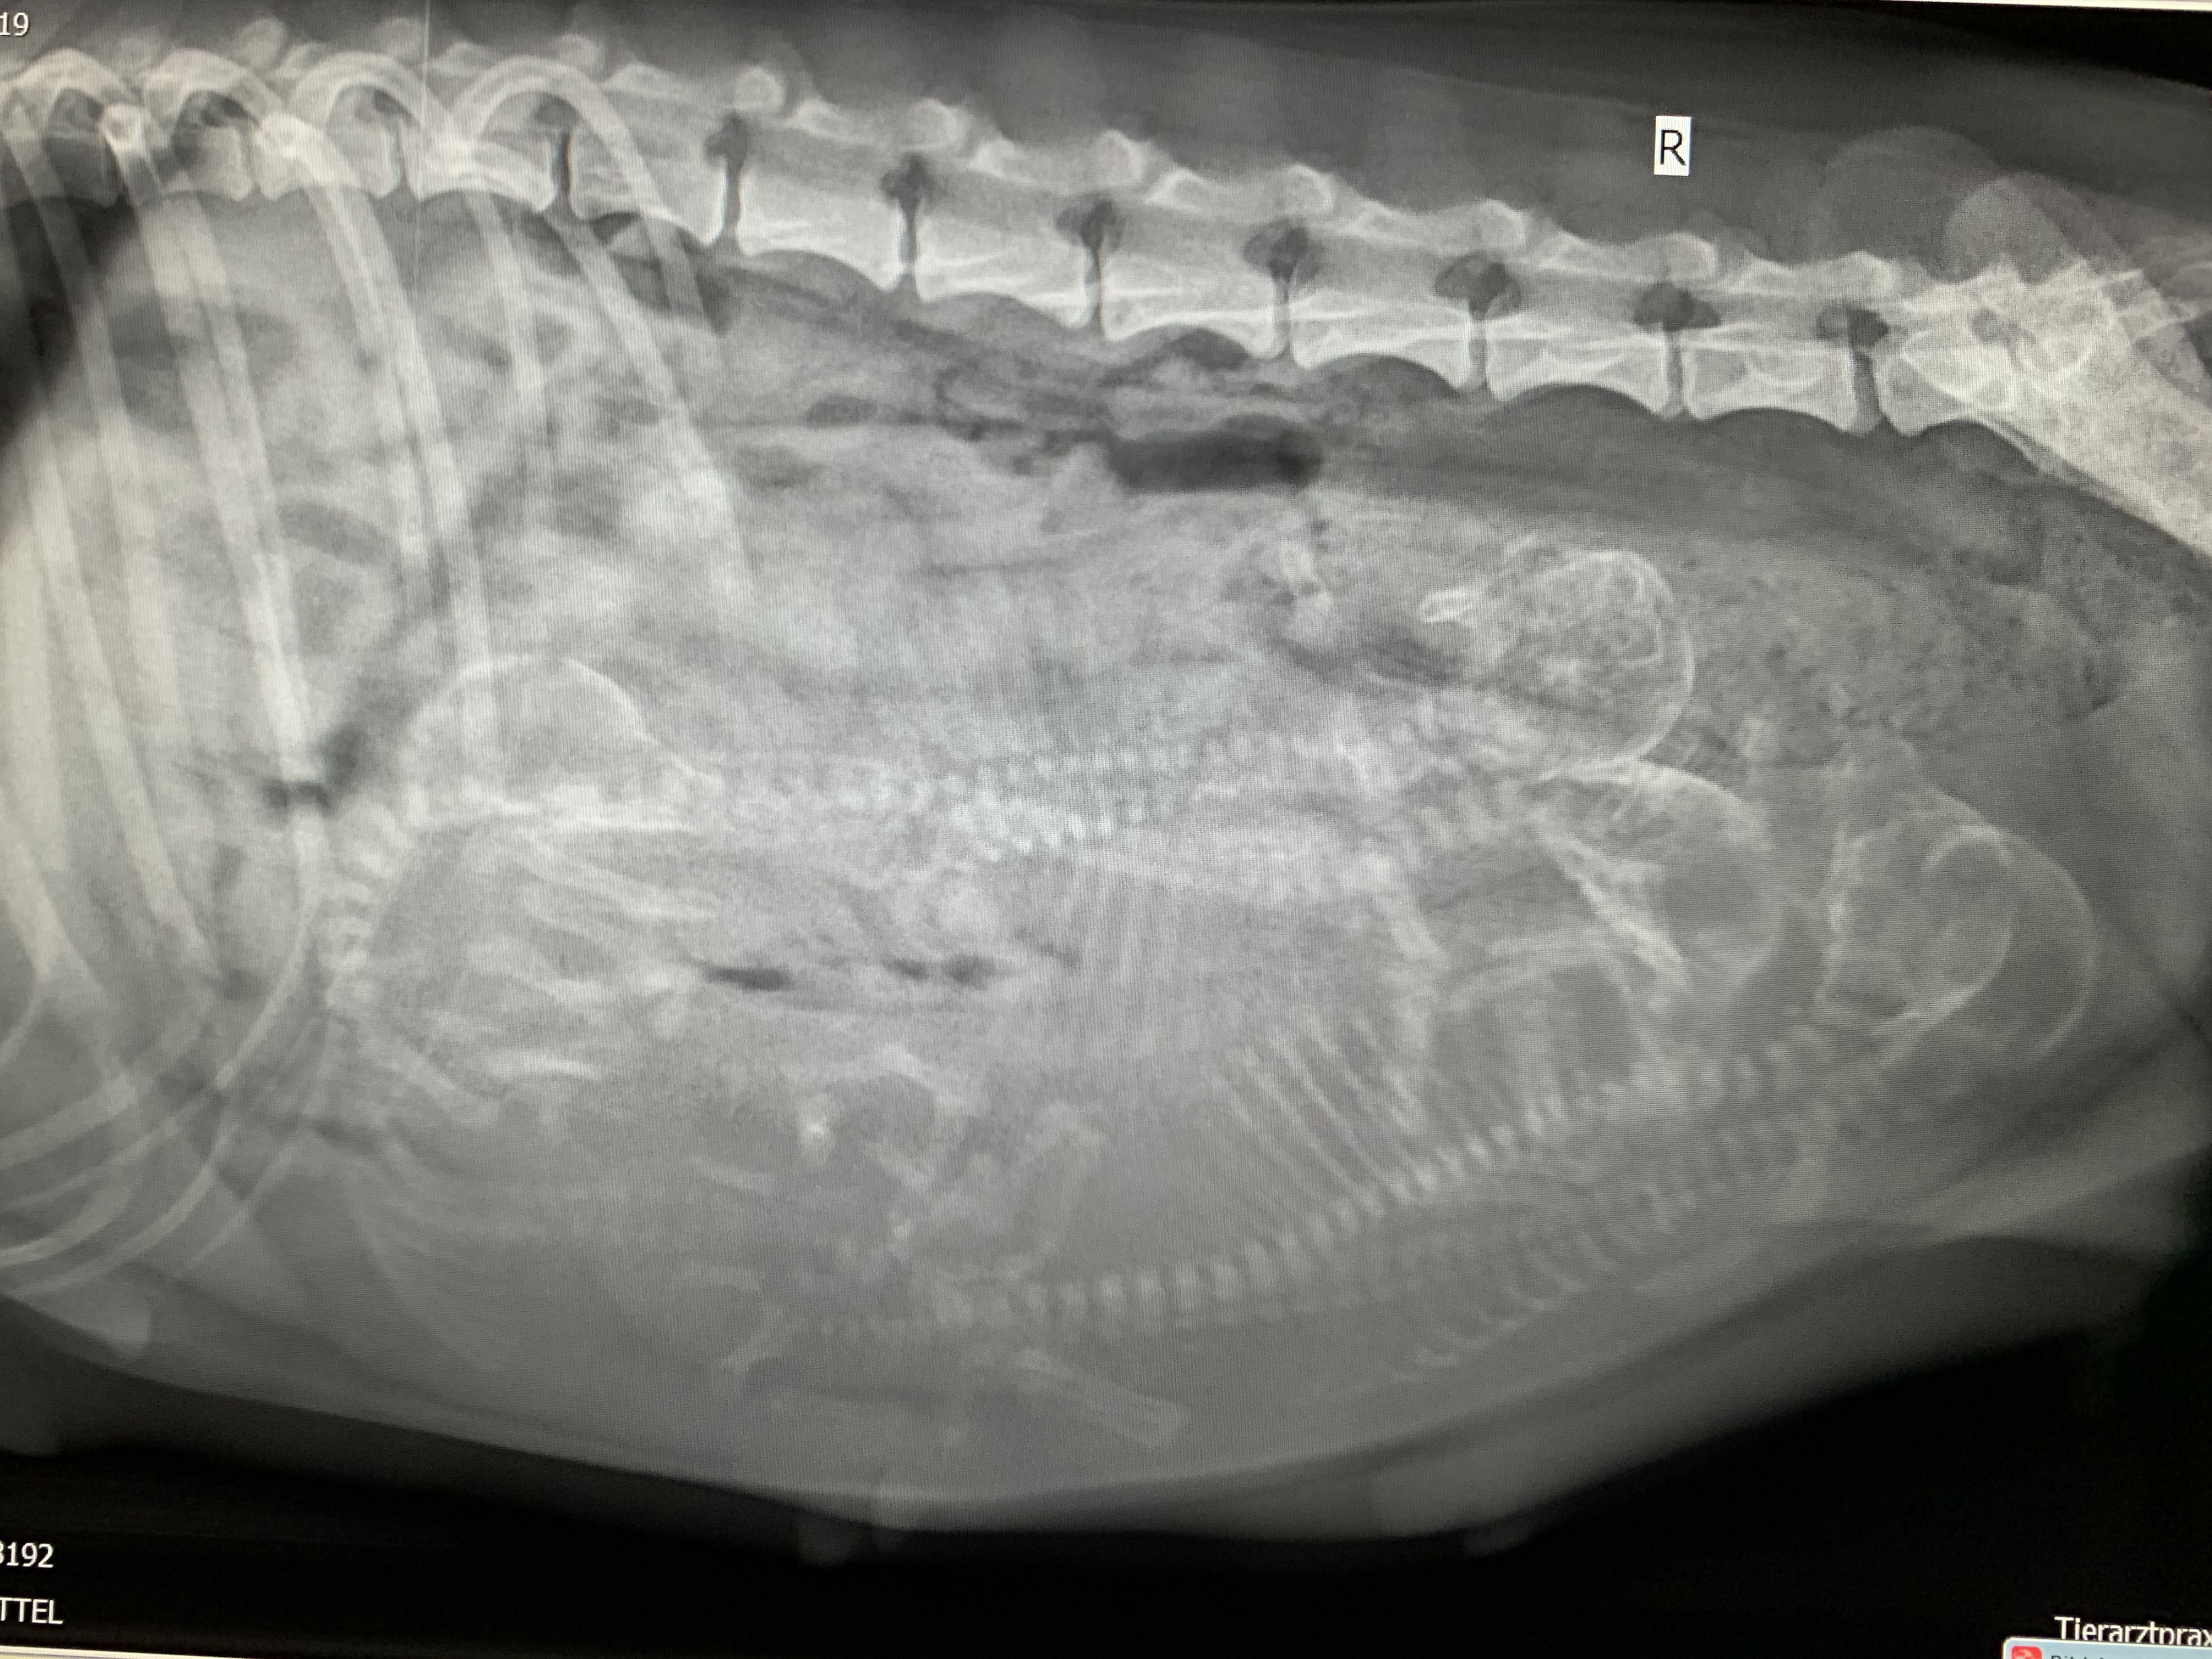

Hier noch ein paar Eckdaten zu den Mamas von heute :-). Wer von den beiden dann nun final unseren W oder X Wurf zur Welt bringt, werden wir bald wissen. Und damit ihr alle auch was zu tun habt, könnt ihr gerne mal Zählen - ich habe bewußt die Anzahl Welpen hier nicht mit angegeben. Mit den Bildern verabschieden wir uns dann mal bis nach der Geburt von W und X Wurf .......

Ella - Tag 56 - + 3,2kg somit aktuell 17,6 kg